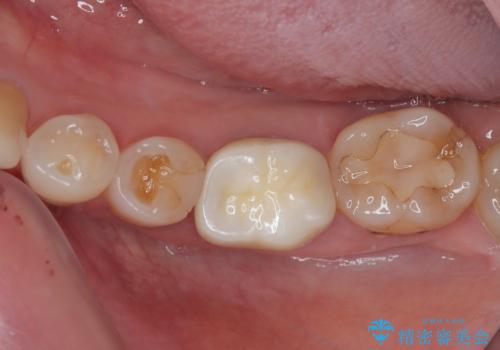

奥歯がたまにしみる フルジルコニアクラウンの補綴治療